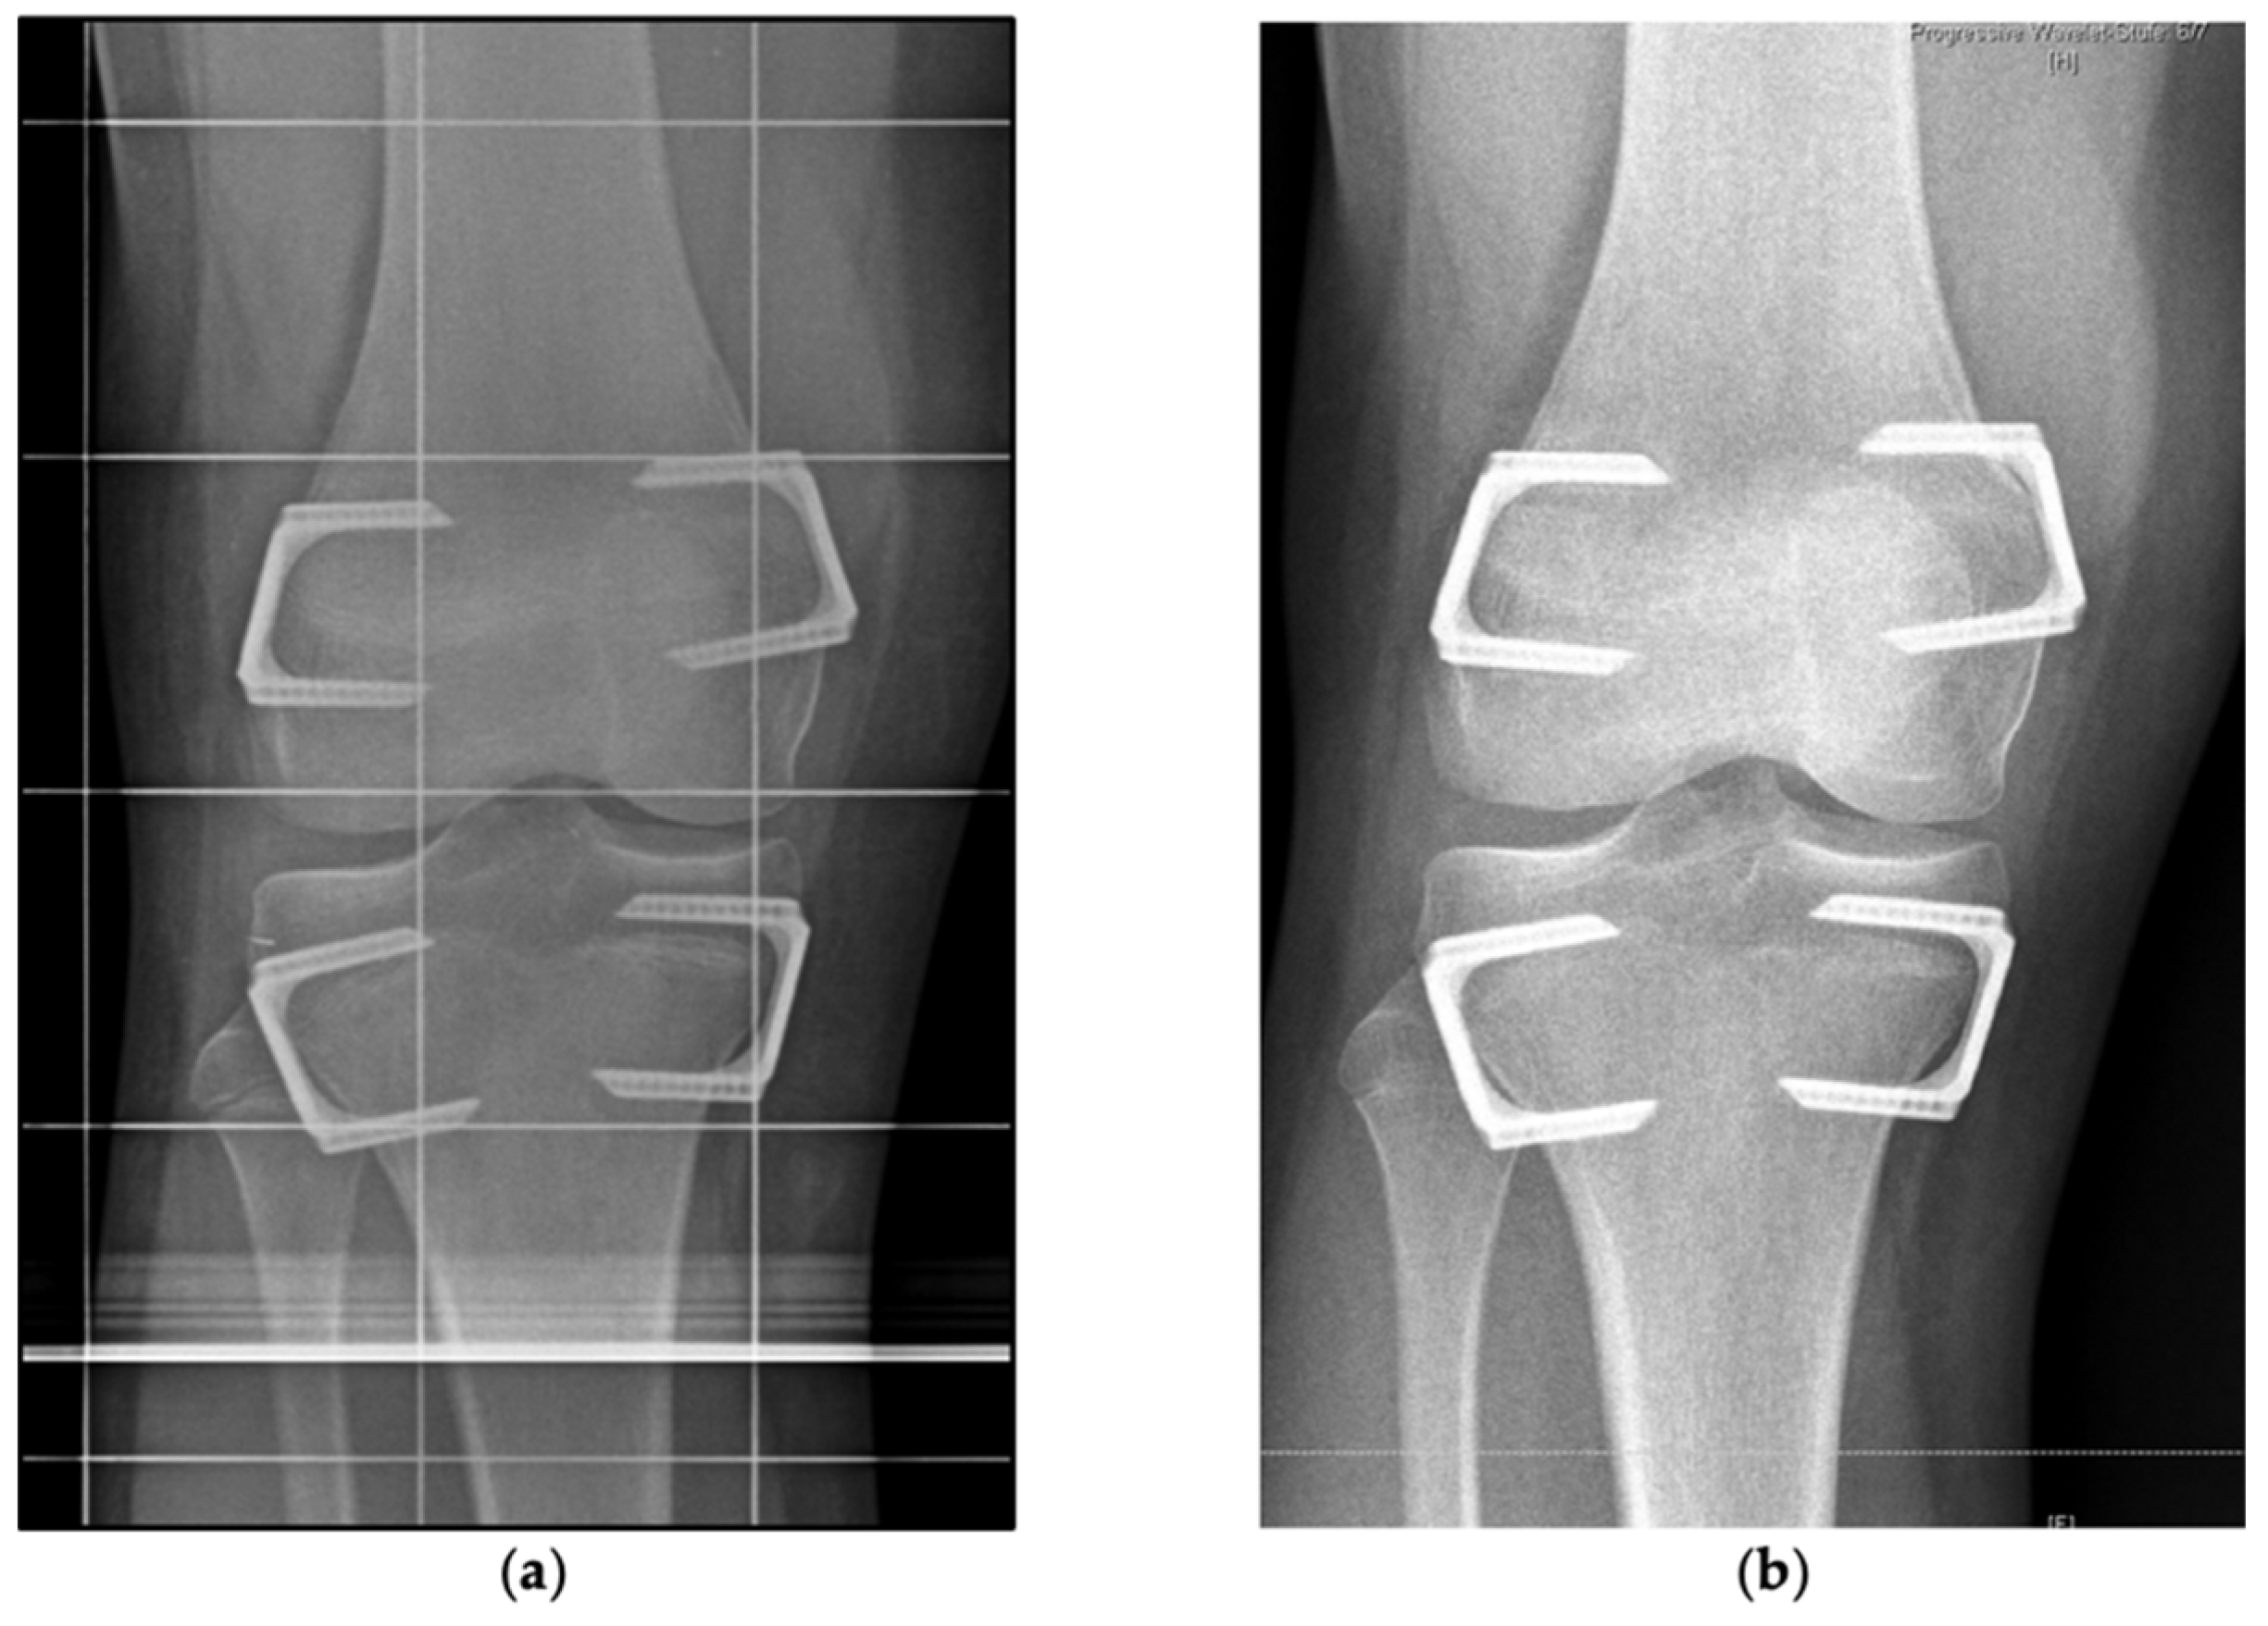

2.2. Indication, Operative Technique, and Applied Implants

2.3. Implants Applied for Epiphysiodesis